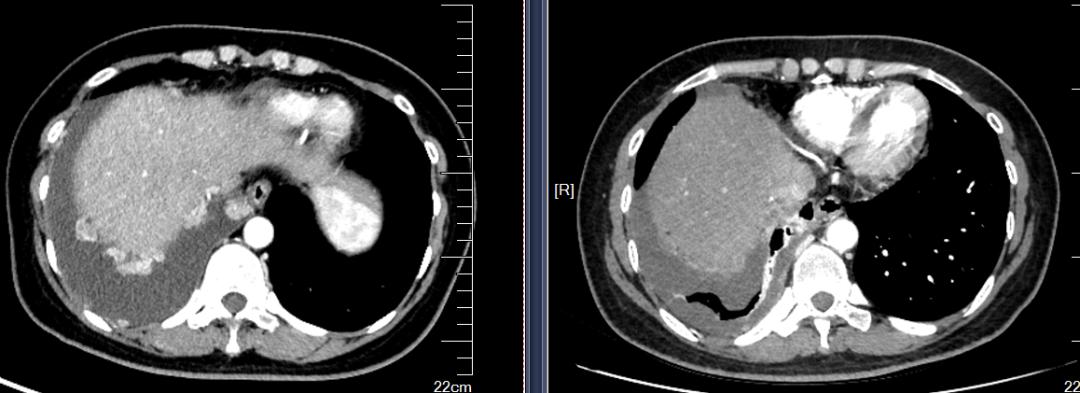

2020-10开始行PD-1抗体联合抗血管生成治疗3周期,顺铂60mg胸灌,继予红色诺卡氏菌细胞壁骨架600ug胸腔灌注2次。予红色诺卡氏菌细胞壁骨架200μg每周一次皮下注射6次。2020-11查CT胸水较前大幅减少,肿瘤标志物较前下降,原有咳嗽、胸痛症状减轻。

左图(2020-10-09), 右图(2020-12-22)